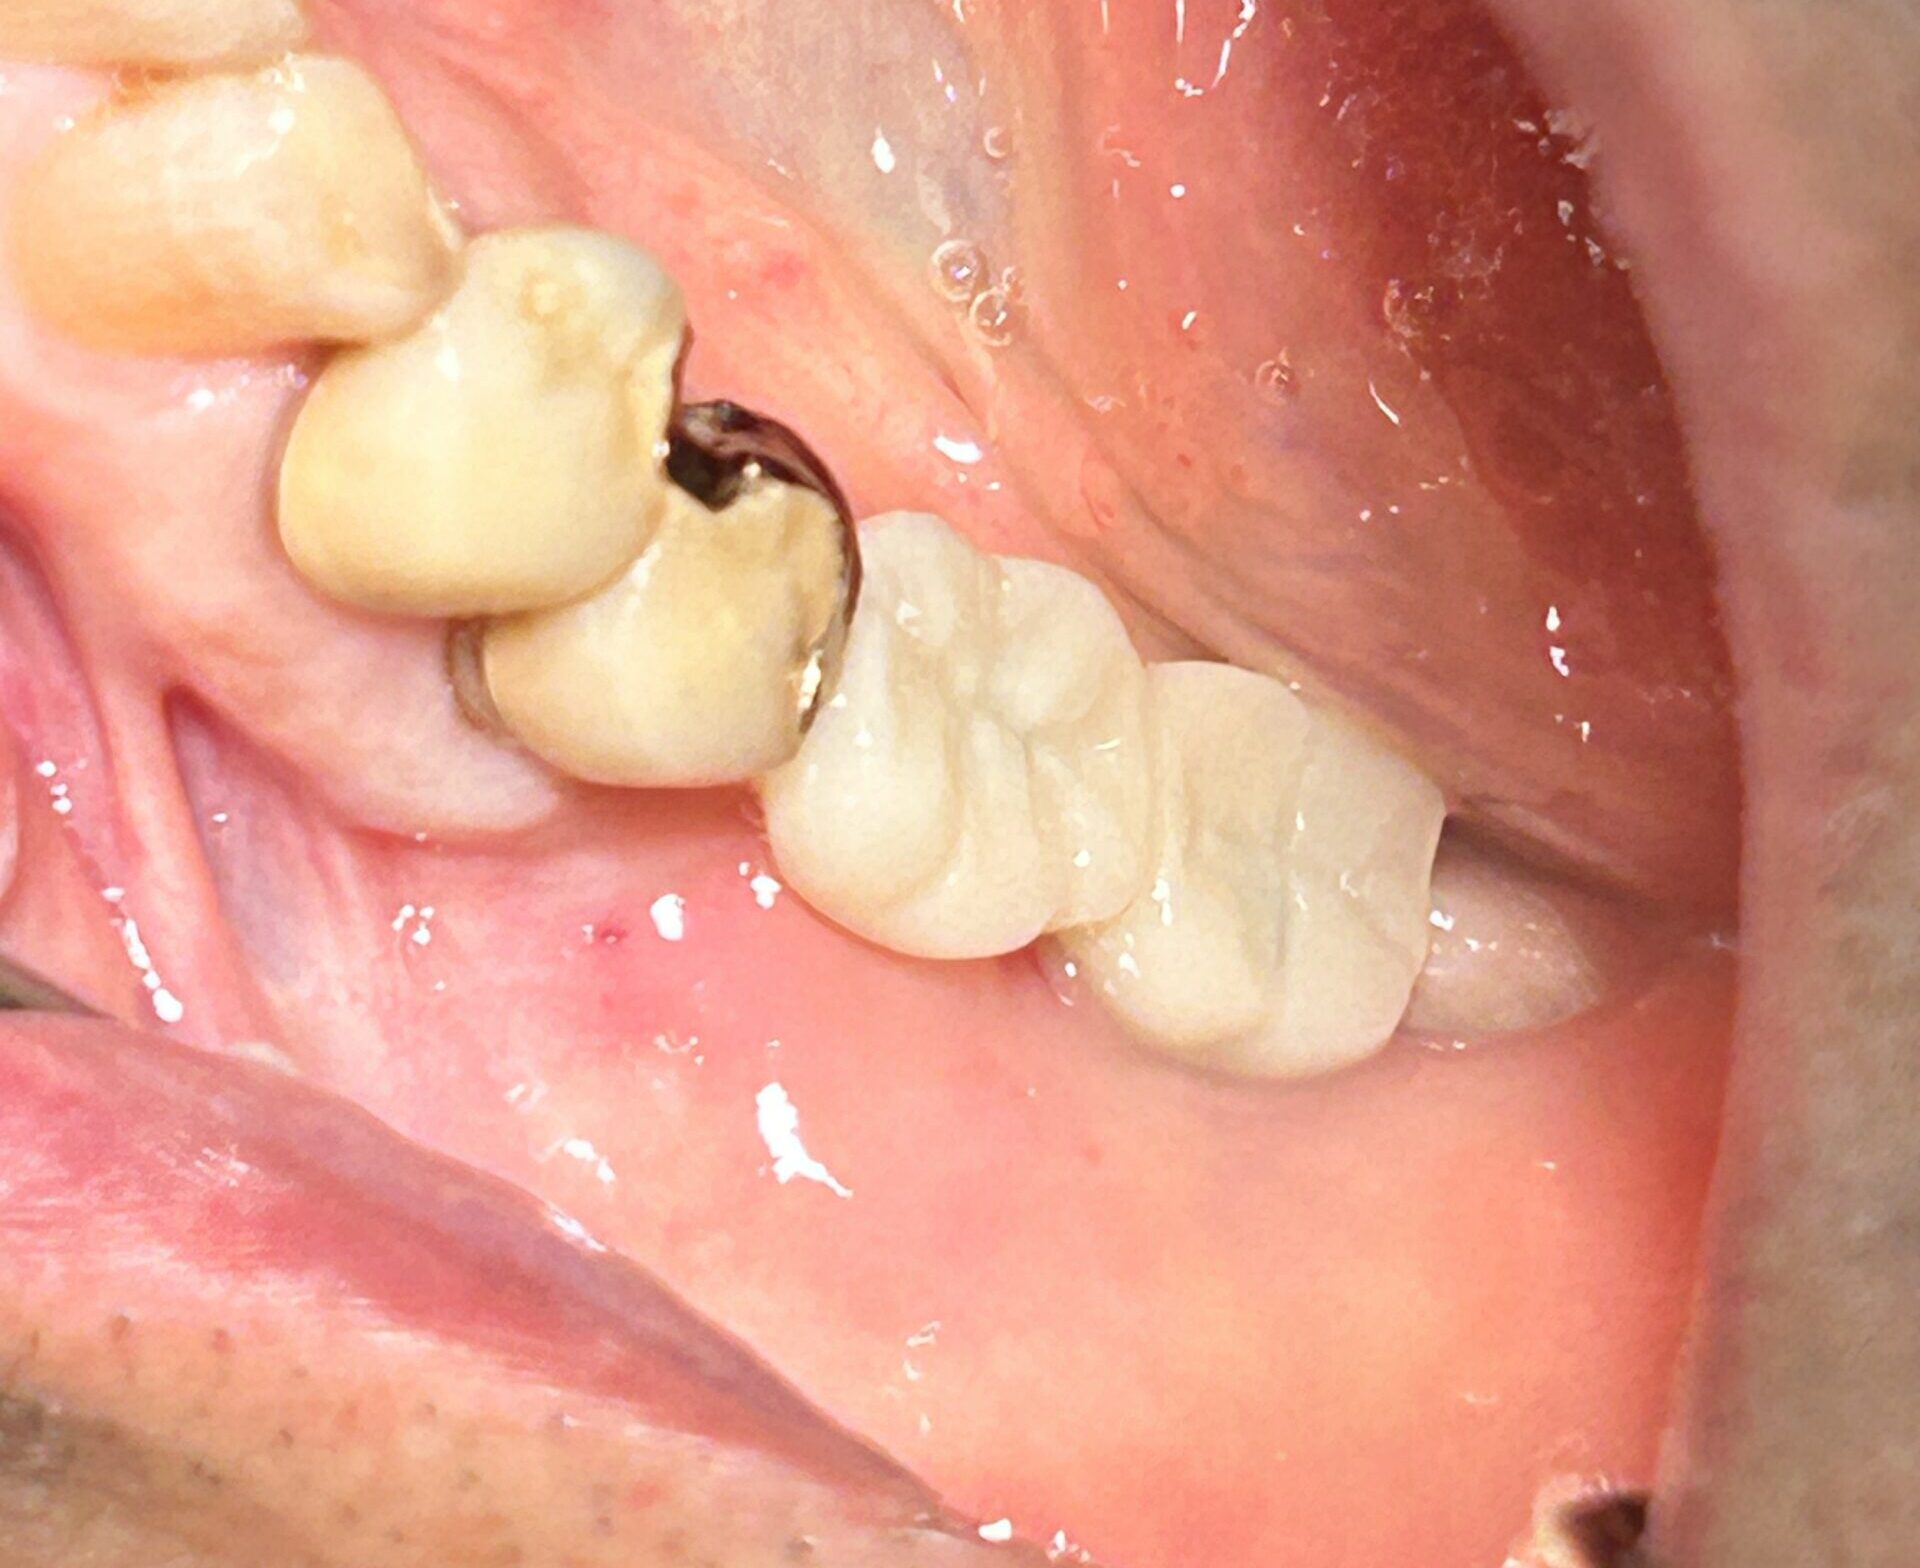

抜歯窩保存術(ばっしかほぞんじゅつ)

歯を抜いた後の穴(抜歯窩)は、そのままにすると骨が大幅に痩せてしまいます(横に約3mm、縦に1mm以上)。

-

内容: 抜歯と同時に人工骨などを補填し、骨が減るのを最小限(横1mm程度)に抑えます。

メリット: 将来のインプラント手術がスムーズになり、見た目も美しく保てます。